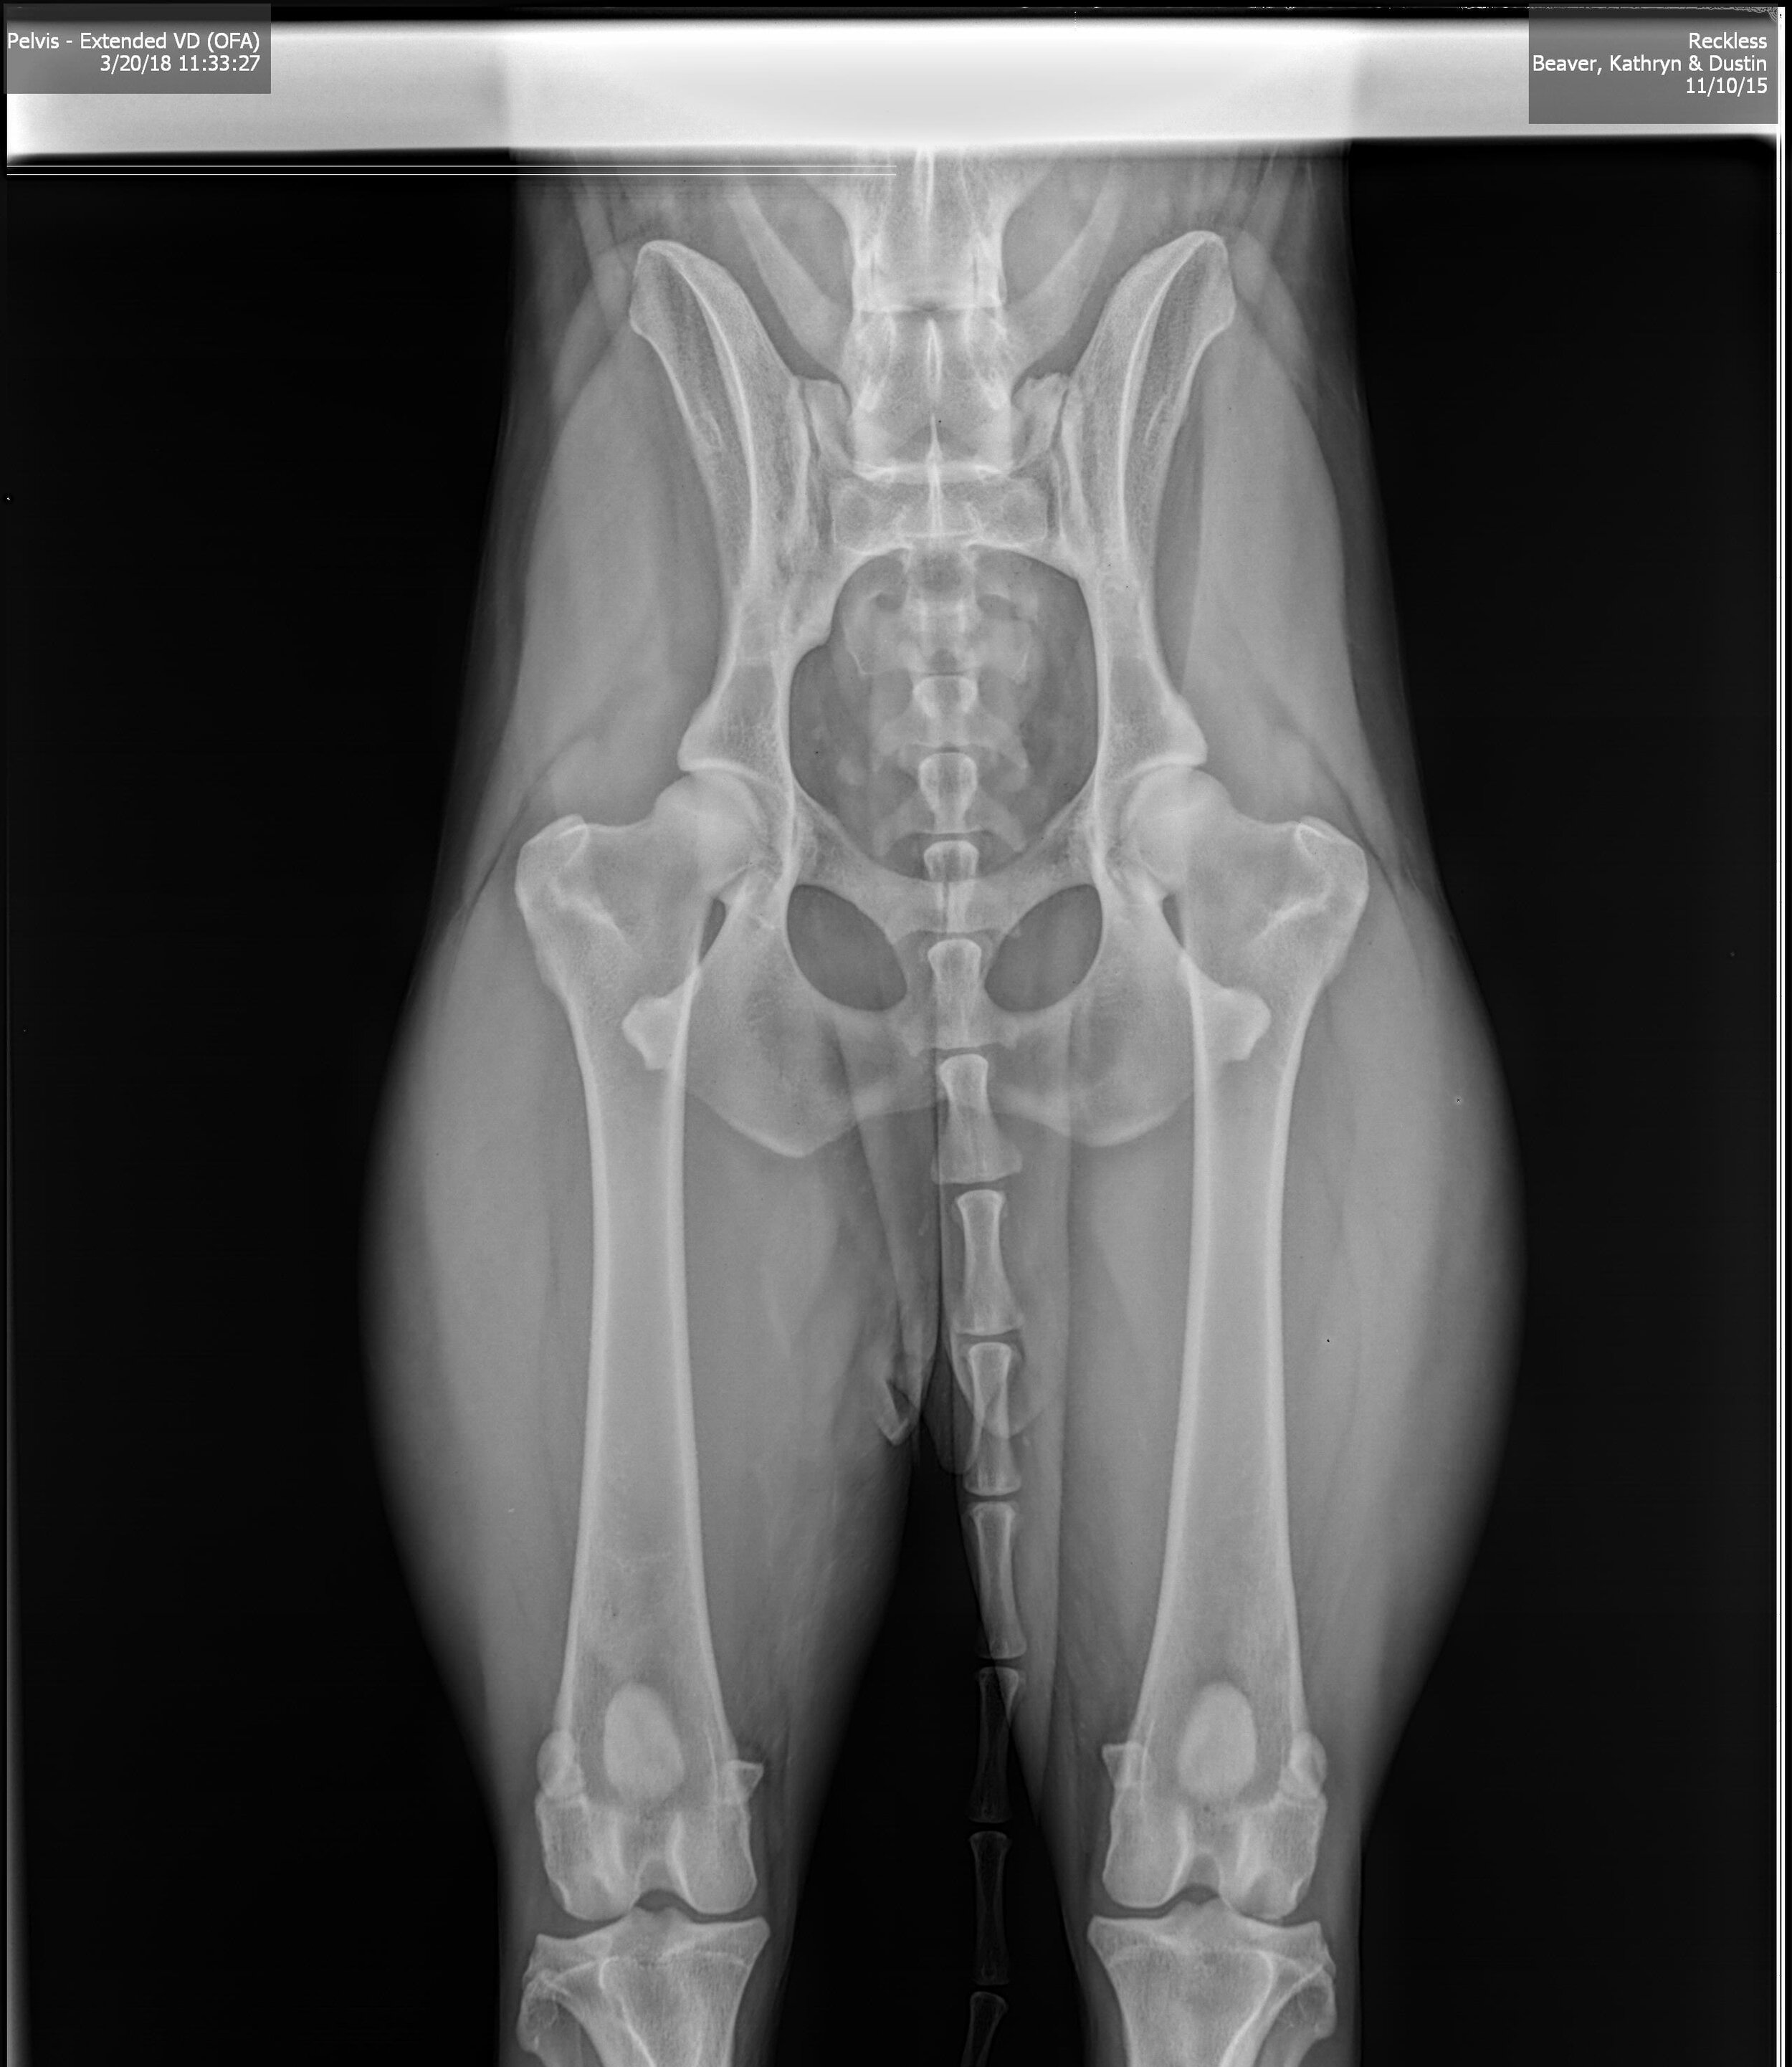

OFA Hip X-ray Certification

Professional OFA hip evaluation X-ray showing excellent joint structure

Orthopedic Foundation Certifications

All breeding animals receive official certification through the Orthopedic Foundation for Animals (OFA). These evaluations are performed by certified veterinarians and provide crucial information about joint health and development.

Hip Dysplasia Screening

X-rays evaluated at 24+ months of age for hip joint structure and development. We only breed animals with ratings of Good, Excellent, or Fair.